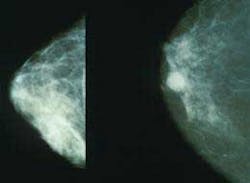

1. What type of breast cancer do I have? What is the location? Is it infiltrating or invasive, or noninvasive?

2. What is the size of the tumor?

3. Has the cancer spread (metastasized) to the lymph nodes?

4. What is the stage of the breast cancer? The TNM staging system that is the most common one used to describe the stages of breast cancer is the AJCC/TNM. This system takes into account the tumor size and spread (T), whether the cancer has spread to lymph nodes (N), and whether it has spread to distant organs (M, for metastasis). Numbers after the T, N, and M give details about the cancer.(4) This is necessary to determine the type of treatment.